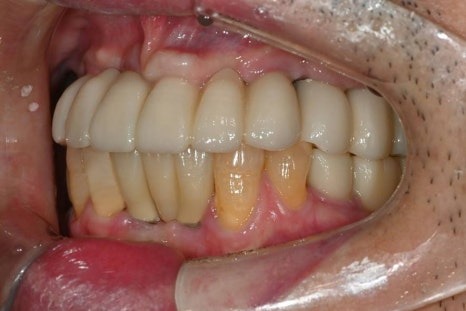

당뇨·고혈압을 모두 가지고 계셨던

전악 임플란트 케이스

이번에 소개해드릴 환자분은

당뇨와 고혈압, 두 가지 전신질환을

모두 가지고 계셨던 분으로

치아 결손이 광범위해

전악 임플란트가 필요한 상황이었습니다.

· 상악은 잇몸뼈가 매우 얇고 치아가 거의 남아 있지 않은 상태

· 하악은 부분 결손과 앞니의 심한 동요

· 식사가 어려울 정도로 기능 저하가 심한 상태

수술 후 4개월

수술 후 6개월 후 보철완료

치료 전 / 치료 후